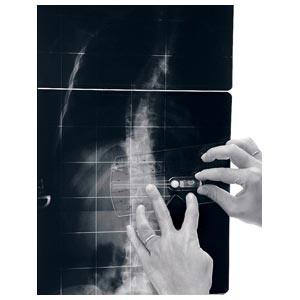

Strumento per la misurazione dell'angolo di Cobb e del gibbo. L'inclinometro è costituito da 1 elemento quasi-rettangolare di plexiglas recante una scala goniometrica, al cui centro è posizionata una piccola asta libera di ruotare e recante una bolla; l'estremità libera dell'astareca l'indice di lettura per la scala goniometrica. Il lato più lungo del rettangolo presenta una rientranza per renderne più agevole l'applicazione sul paziente (nel caso in cui le spinose siano sporgenti).

L'inclinometro è uno strumento manuale, normalmente utilizzato in due situazioni cliniche: • nella misurazione dell'angolo di rotazione del tronco durante il test di anteroflessione • nella misurazione dell'angolo di Cobb sulle radiografie (sia in proiezione AP che LL), quindi sia nella scoliosi che nella cifosi/lordosi.

Un vantaggio dell'inclinometro sugli altri strumenti è dato infine dalla possibilità di misurare sia l'angolo di rotazione del tronco (gibbo) sul paziente, sia l'angolo di Cobb sulle radiografie con un solo semplice strumento.